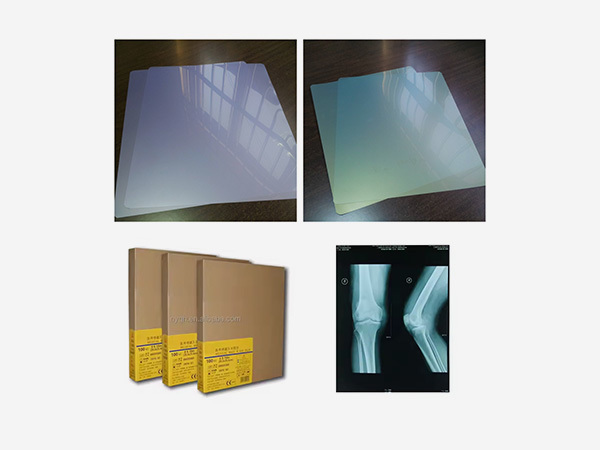

Independently develops and produces thermal film, medical laser film, and medical printing Film and other products.

Nanyang Qinghe Medical Technology Co., Ltd. was established in 2019. It is a technology-based enterprise engaged in the research and development, production and sales of medical films. The company has a factory area of 2,000 square meters, has independent intellectual property rights, has obtained 3 invention patents, 16 utility model patents, has a trademark registration certificate for the "Jiangying" brand, and independently develops and produces thermal film, medical laser film, and medical printing. Film and other products. The company's service personnel and technicians have been working for more than ten years and serve more than 600 medical customers and medical institutions in China. The products are exported to ten ASEAN countries, five Central Asian countries, South Asia, South America, Africa and other regions. The products and The service is widely praised, and there are many service cases from well-known foreign medical institutions.

As an indispensable and important tool in the medical diagnosis process, medical film plays a crucial role in disease detection, diagnosis, and treatment tracking.

Digital medical films use electronic sensors to capture and store images, eliminating the need for chemical processing. They offer faster image acquisition, easy sharing across platforms, and long - term storage without degradation, unlike traditional films that rely on silver halide emulsion and physical storage.

Common types include X-ray films, CT films, and MRI films. X-ray films are used for general radiography, while CT and MRI films display detailed cross-sectional images of the body, aiding in accurate diagnosis and treatment planning.

Independently develops and produces thermal film, medical laser film, and medical printing Film and other products.